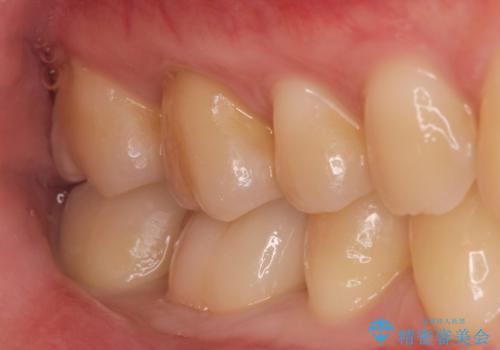

プラスチック樹脂は経年劣化して割れやすく、また虫歯の再発のリスクが高いです。

ジルコニアクラウンは劣化しにくく虫歯の再発のリスクが低いです。

白い被せ物が入りとても満足して頂けました。